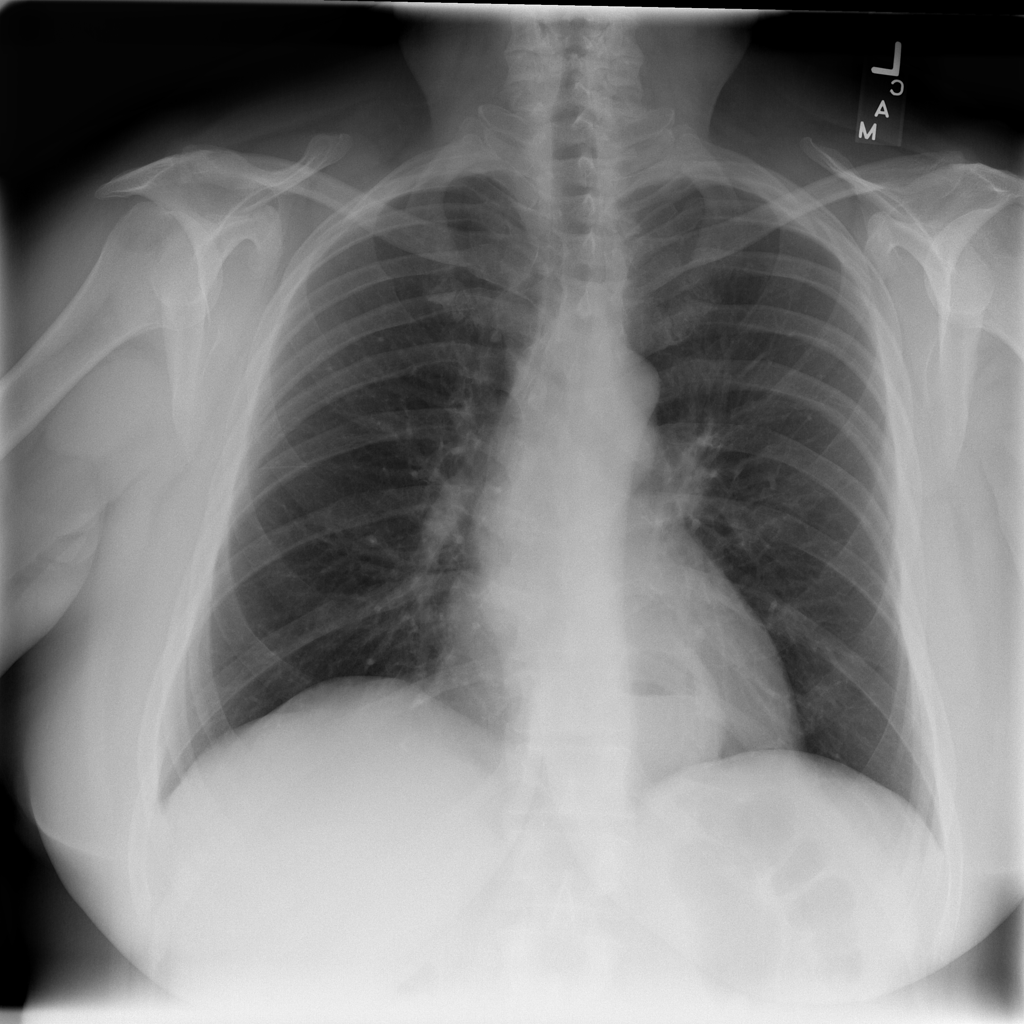

PAT-C048 · IMG-000Hernia

PAT-C048 · IMG-000

PA